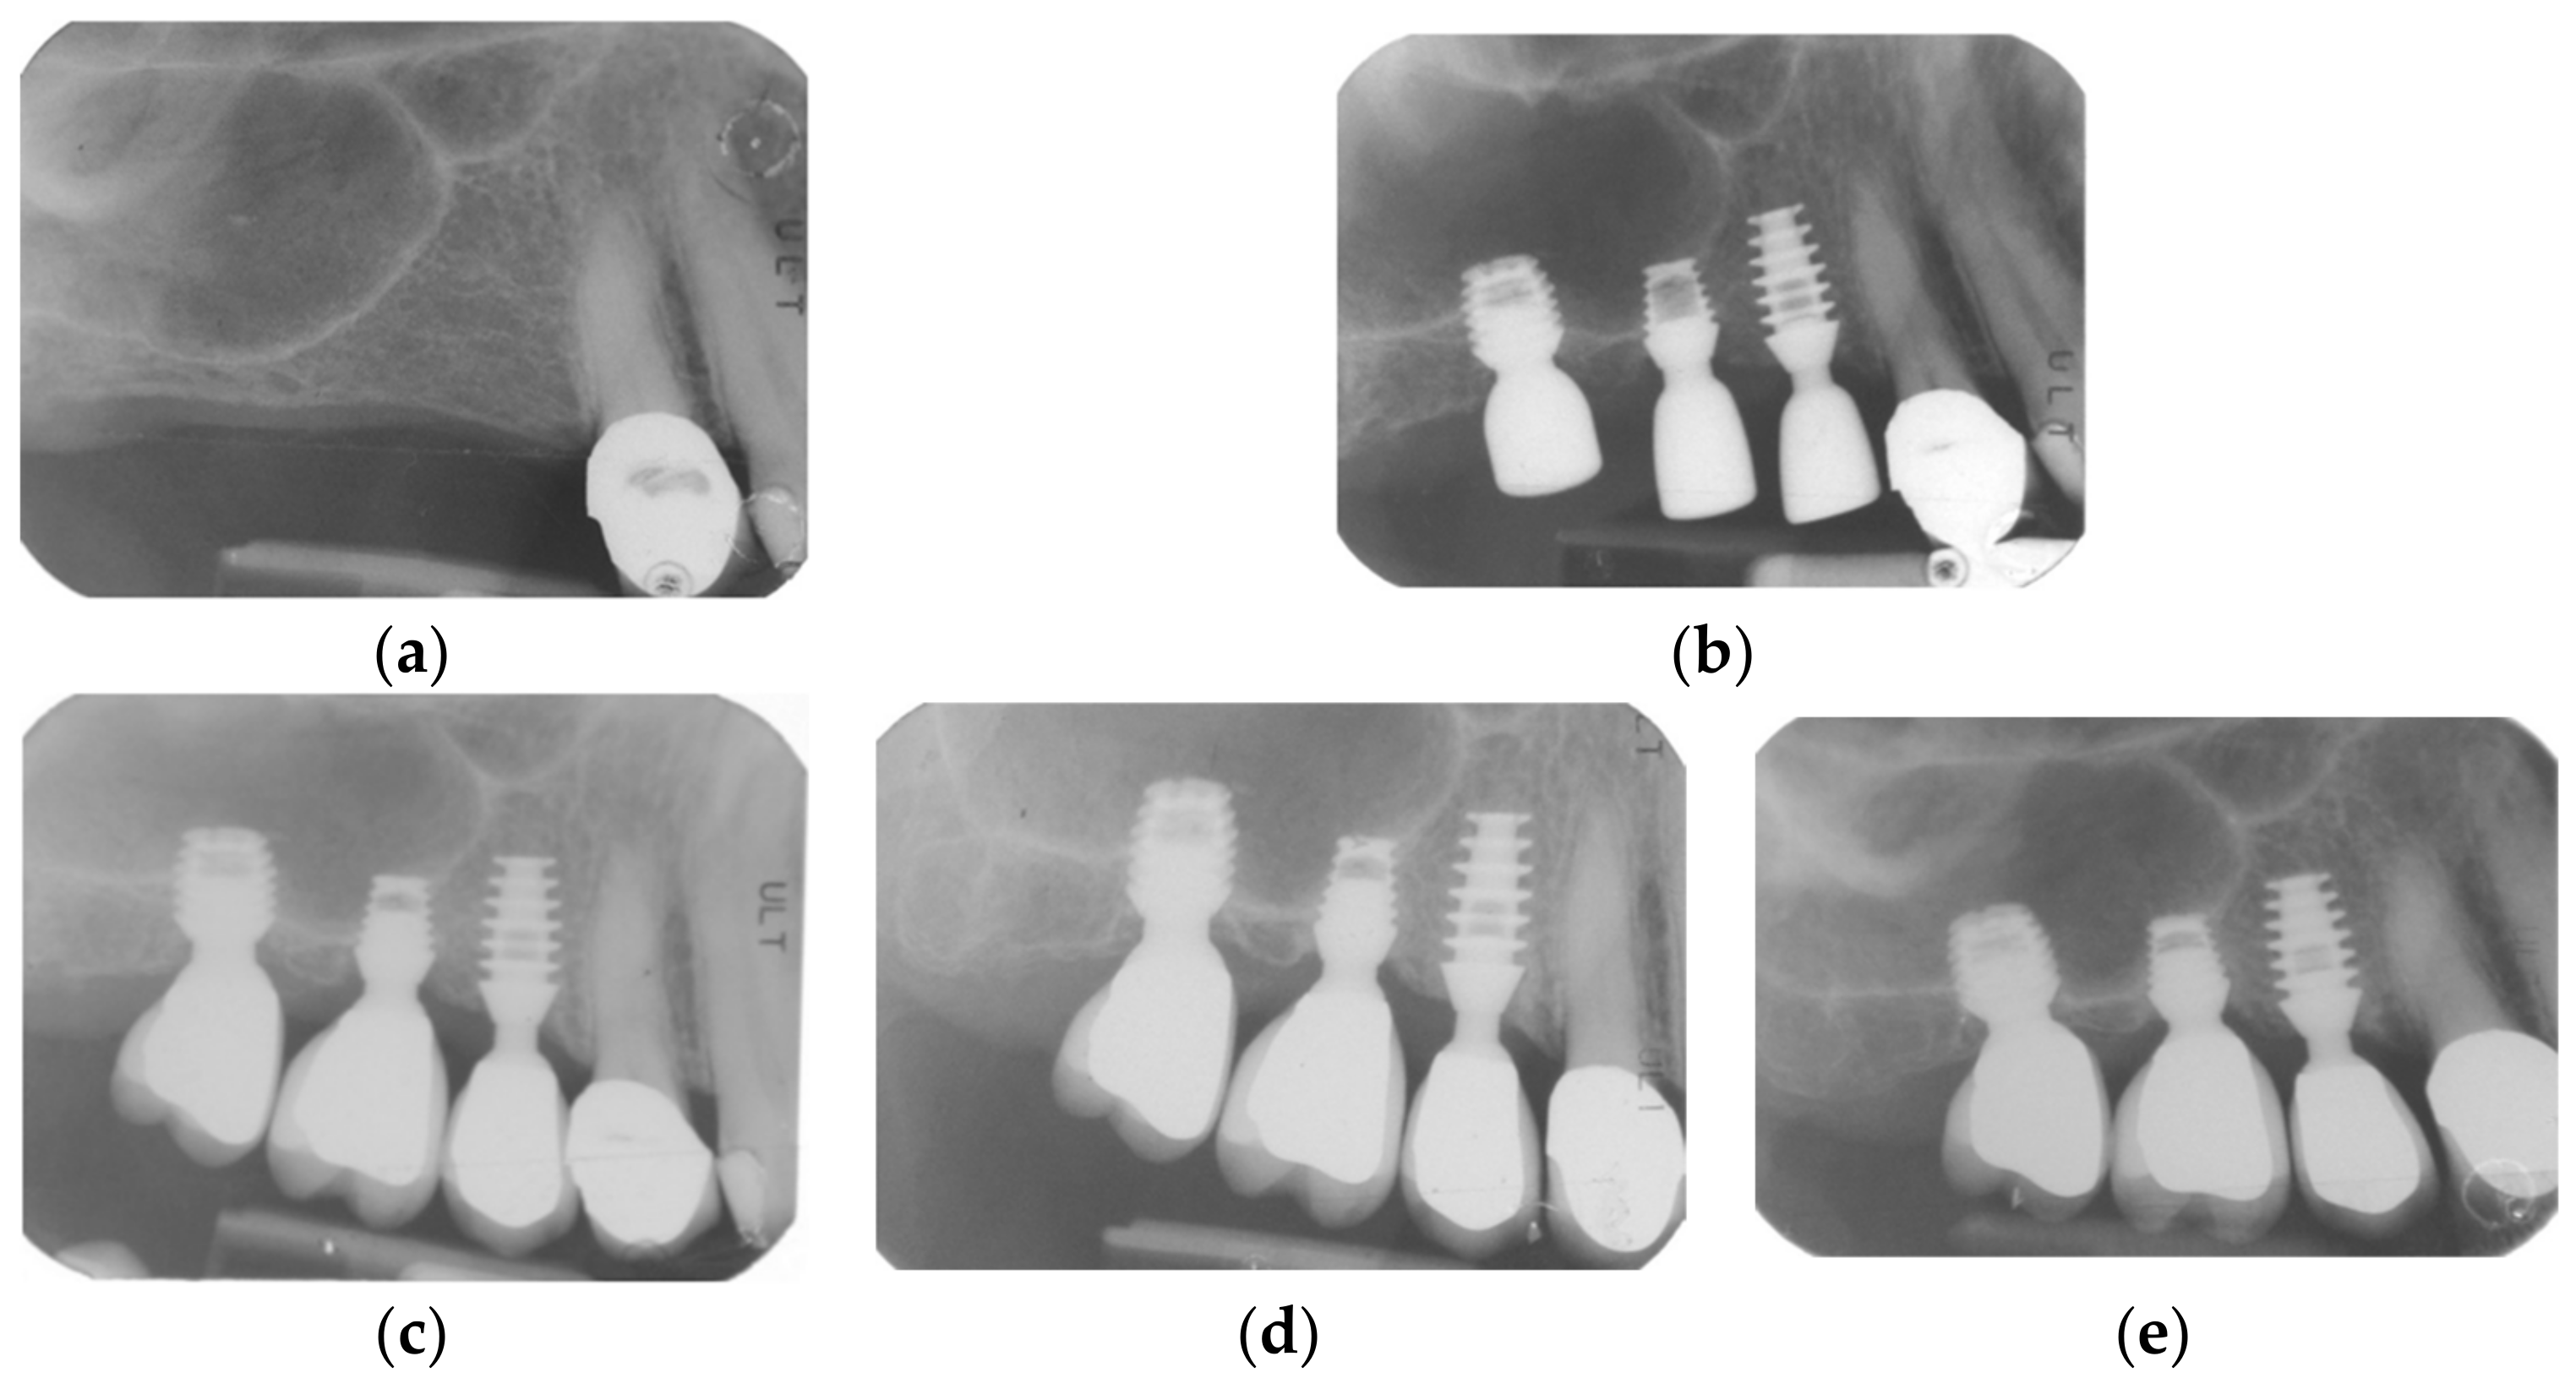

2.2. Surgical Protocol

2.3. Prosthetic Protocol and Follow-Up Evaluation

3.3. Radiographic Bone Levels

3.4. Patients’ Level of Satisfaction